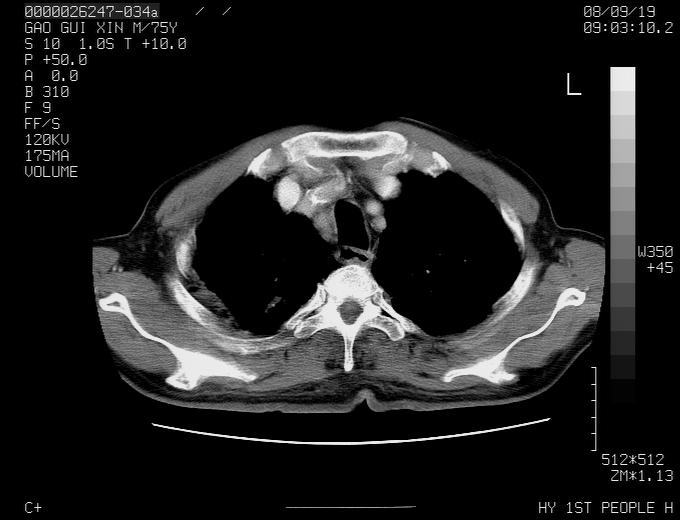

感谢各位老师的意见,左上肺病灶,我本人趋向结核,原因:左上肺见两个类圆形结节,仔细回顾4月份ct似乎原片在该处有条片状密度增高影,强化不明显。

现上传增强片,请各位老师仔细帮我看一下。

右上肺可见条索状影,并可见钙化,左上肺结节可以考虑为结核球,但气管前腔静脉后有肿大淋巴结,本人觉得左上肺结节不能排除转移瘤的可能,右上肺为陈旧性结核灶。

左肺上叶周围性肺癌并纵隔多组lnm.不可能是tb.

左肺上叶尖段瘢痕癌并纵隔淋巴结转移解释更好一些.

双上肺继发型肺结核,纵隔淋巴结结核可能性大,建议定期复查.

左肺周围癌并纵隔淋巴结转移,另一小结节是血管影

别再ct讨论了,一个纤支镜检查马上明确.肺癌不会错的!应该是低分化鳞癌.

左上肺周围型肺癌并纵隔淋巴结转移

1)左肺上叶尖段周围型肺癌并纵隔淋巴结转移。2)冠状动脉及主动脉钙化。

左上肺周围型肺癌并纵隔淋巴结转移。纤支镜检查